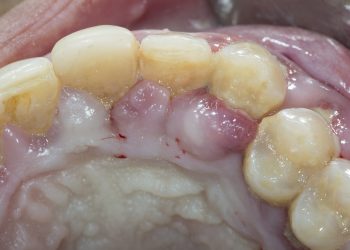

Introduction Gum disease, also known as periodontal disease, is a progressive condition that affects the tissues supporting the teeth. It ...

Introduction Periodontal disease is a common oral disease that affects the oral health of hundreds of millions of people worldwide. ...